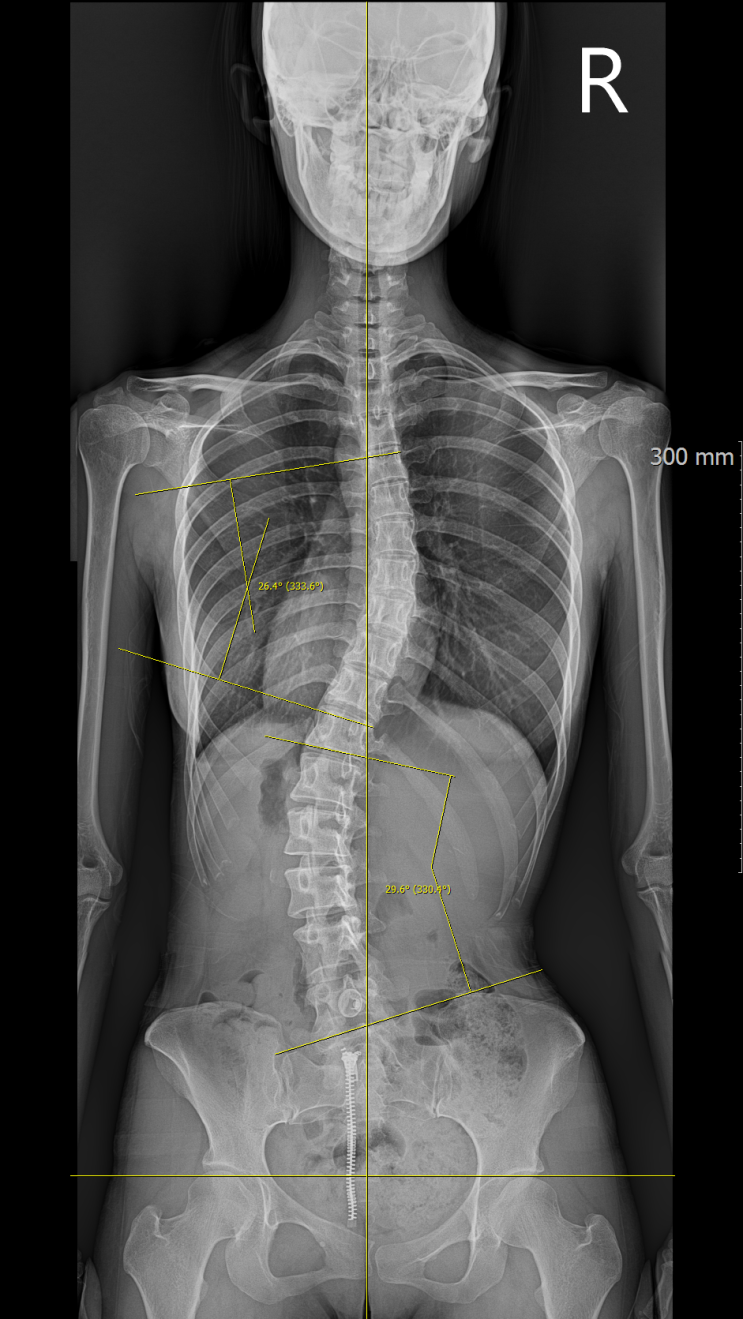

수원 청소년 척추측만증(척추옆굽음증), 코어 운동은 어떤 영향을 미칠까?

안녕하세요 척추측만증 전문 물리치료사 김동현입니다. 오늘은 근거를 기반으로 청소년 특발성 척추측만증...

수원 척추측만증(옆굽음증)과 허리디스크 도수치료를 받아야 할까?

안녕하세요 척추측만증(옆굽음증)전문 물리치료사 김동현 입니다. 오늘은 척추측만증과 디스크에 대해서 알...

봉담 정형외과 척추측만증(옆굽음증) 치료는 어디가 좋을까요?

안녕하세요 척추측만증(옆굽음증) 전문 물리치료사 김동현입니다. 저는 척추측만증(척추옆굽음증) 전문 물...

척추측만증(척추옆굽음증)을 가진 사람들이 운동화 한쪽만 닳는 이유와 다리길이 차이

척추측만증(척추옆굽음증)을 가진 사람들은 남녀노소 할 것 없이 운동화의 한쪽만 닳는 경우를 경험하실 수...